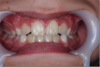

Lorenzo 10 ans : 6 mois d'éducateur fonctionnel